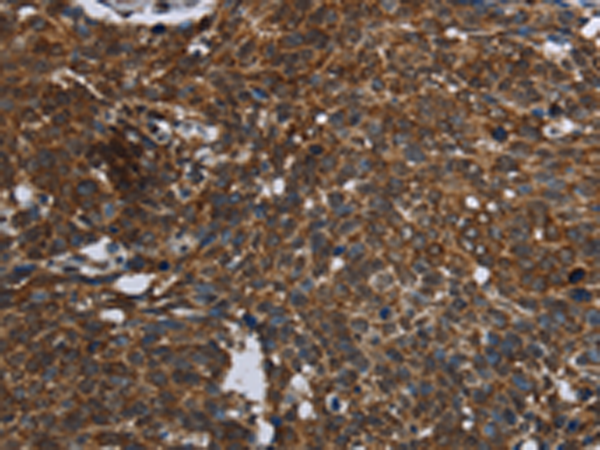

分类: 科研抗体货号: P08321别名:应用: IHC反应种属: Human, Mouse, Rat

分类: 科研抗体货号: P08304别名: D5D; TU12; FADS6; FADSD5; LLCDL1应用: WB,IHC反应种属: Human, Mouse, Rat

分类: 科研抗体货号: P08310别名: MTVR1应用: WB,IHC反应种属: Human, Mouse

分类: 科研抗体货号: P08301别名: AMDD应用: IHC反应种属: Human

分类: 科研抗体货号: P08320别名: FBP应用: WB,IHC反应种属: Human, Mouse

分类: 科研抗体货号: P08309别名: 2-21; ORF9; PANDER; PRED44; C21orf11; C21orf76应用: IHC反应种属: Human, Mouse

分类: 科研抗体货号: P08300别名: CVL; CVIL; VIL2; HEL-S-105应用: WB,IHC反应种属: Human, Mouse, Rat

分类: 科研抗体货号: P08335别名: DRAL; AAG11; FHL-2; SLIM3; SLIM-3应用: WB,IHC反应种属: Human, Mouse, Rat

分类: 科研抗体货号: P08318别名: KIAA0971应用: WB,IHC反应种属: Human